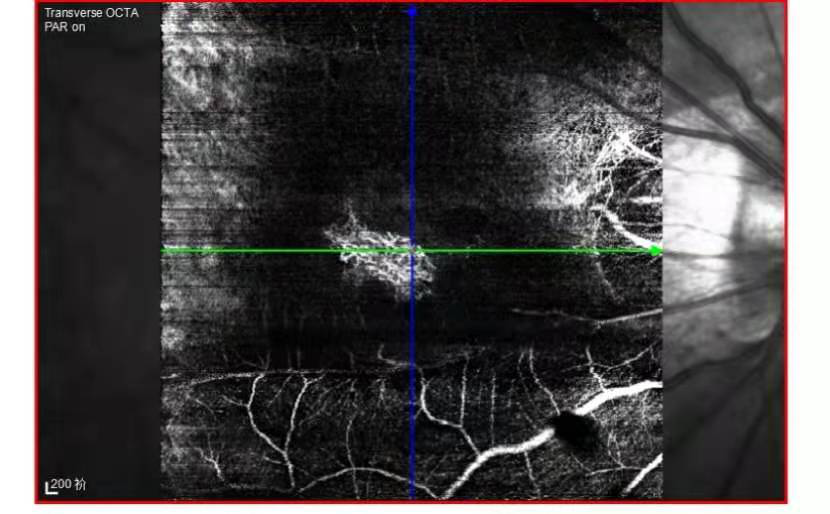

而光学相干断层扫描血管成像技术(OCTA)作为一种新型的成像技术,弥补了OCT对视网膜血管监测的不足,可以在活体上观察微血管的改变,并能分层观察每一层的视网膜和脉络膜血管,定量测量血管密度。也是无创的检查,比如在诊断脉络膜新生血管膜时,如果患者的身体条件不能做眼底血管造影检查,可以做OCTA检查,来观察新生血管膜的位置、形态及范围,是目前AMD鉴别诊断的主要工具。

OCTA检查图像